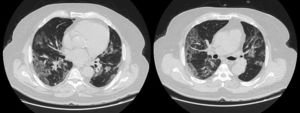

LDH has a significant positive correlation with the severity of pneumonia quantified on initial computed tomography (CT) in COVID-19 patients.11 Patients with severe disease presented higher levels at admission than those with a non-severe disease.12 Hence, LDH indicates the severity of tissue damage and the risk of worsening. The most characteristic chest CT abnormalities in COVID19 pneumonia were pure ground-glass opacities (GGO) (Supp. Figure 2) or mixed with consolidation (supp. Figures 3-4) or a reticular pattern, usually multifocal, asymmetric, bilateral, and peripheral, most commonly located in the inferior lobes.13 GGO is a radiological term revealing an area of increased, hazy lung opacity through which bronchial structures and vessels are still visible, consolidation was defined as the presence on a chest CT of opacities with obscuration of the pulmonary vessels’ airway walls.

Chronic kidney disease (CKD) was defined as an estimated glomerular filtration rate (eGFR) of less than 60 mL/min/1.73 m3. Immunosuppression was defined as any condition that could compromise immunity, including treatment with immunosuppressants or oral glucocorticoids (dexamethasone more than 3.0 mg per day) for more than 1 month before hospital admission, chemotherapy within 2 weeks of hospital admission, impaired immunodeficiency, and HIV. Cardiovascular disease included conditions affecting the heart or blood vessels, such as coronary heart disease, cerebrovascular disease, peripheral arterial disease, rheumatic heart disease, congenital heart disease, deep vein thrombosis, pulmonary embolism, and heart attacks or strokes. Admission laboratory results included baseline serum LDH (U/L), ferritin (ng/mL), CRP (mg/L), procalcitonin (μg/L), lymphocyte (/μL), and D-dimers (μg/mL). Chest imaging findings at admission and during follow-up comprised the percentage of ground glass, the presence of lobar consolidation, pulmonary embolism, and pneumomediastinum. Radiological severity outcomes were assessed upon admission and during follow-up using Non-Contrast Computed Tomography (NCCT), which included a semi-quantitative CT score based on the extent of lobar involvement. All CT images were reviewed by a senior radiologist expert in thoracic imaging and 2 fellowship-trained radiologists with approximately 3 years of experience in the Radiology Department at HDF. The baseline chest NCCT was systematically performed, while a contrast CT was ordered in case of clinical suspicion of pulmonary embolism (supp. Figure 1). A follow-up chest CT was performed whenever the patient clinical status worsened despite optimal treatment, pending transportability in critical situations. We evaluated the extension of the ground-glass opacities on chest CT, the number of patients with consolidation and with a mixed pattern. A mixed pattern was defined in our study as a GGO extension greater than or equal to 25%, along with a consolidation pattern.

GGO occupied 26% (8%–44%) of the lung area on baseline chest CT and 40% (14%–66%) on follow-up. Lobar consolidation was found in 38 (8.4%) patients on baseline chest CT and 30 (14.3%) patients on follow-up. Follow-up chest CT showed a higher number of patients with PE and PM than on admission: PE was found in 3 (0.7%) on admission versus 10 (4.8%) patients on follow-up, noting that a contrast chest CT was only done in case of high suspicion of PE. Two (0.4%) patients presented a PM on admission, and 12 (5.7%) had PM on follow-up. A mixed pattern was detected in 21 (4.5%) patients on admission chest CT.